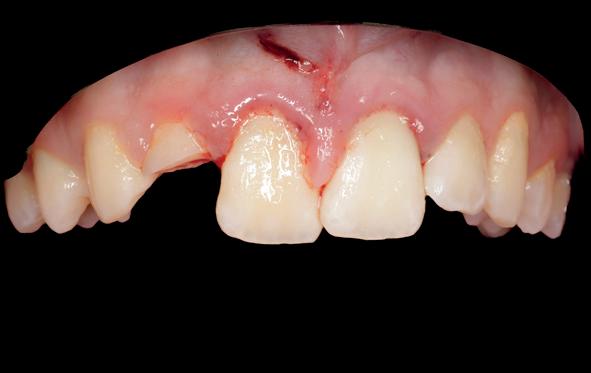

Na het reponeren en voorafgaand aan fixatie van de 11 en 21, heb ik de positie getoetst middels een nieuwe matching (afbeelding 8-9). Hieruit bleek dat 11 en 21 nog iets geïnclineerd moesten worden. Tijdens

het uitharden is er nog druk uitgeoefend op deze elementen om de laatste puntjes op de i te zetten. Daarna is de lip gehecht (afbeelding 10-14).